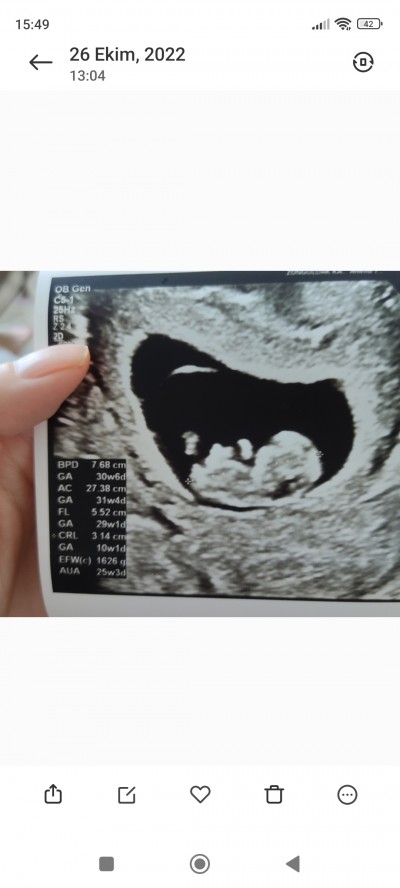

banada bakin

image

sizce benimkinin cinsiyeti ne bide siz yorumlayin:)))

Ben cinsiyetini biliyorum sadece merk ettim ne diceksiniz kel ilac muhabbetine girdigin gibi cik istersen canim benim bebegim erkek:))

Bencede bu bebek kıza benziyor Dr yanılmış olabilir mi